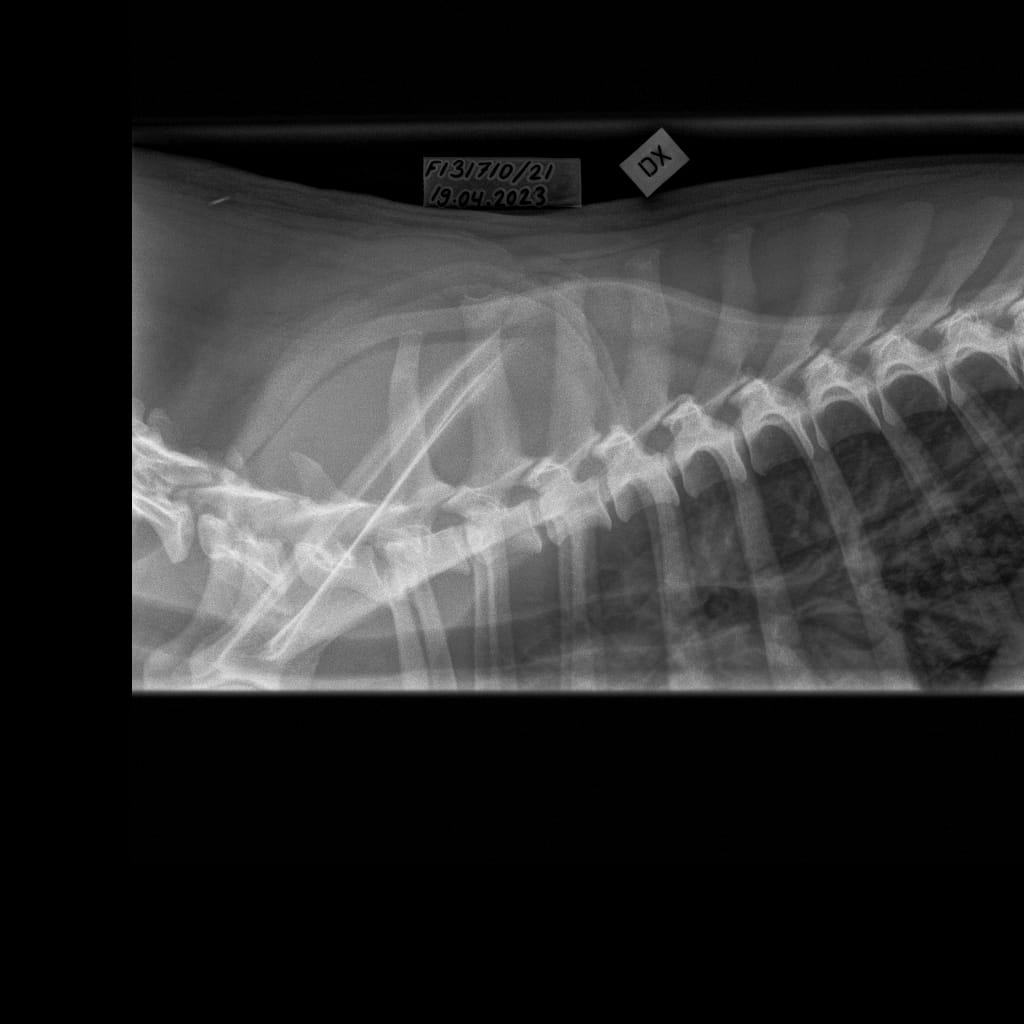

Selkäranka -Rintaranka LAT-6.11.2023-16_02_18-718